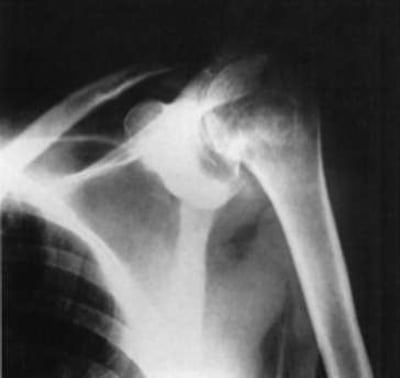

- рентгенография. Необходима для исключения переломов, вывихов и деформирующего артроза. У некоторых пациентов с длительнотекущим капсулитом на рентгенограммах выявляют признаки остеопороза. Причина его развития – продолжительная иммобилизация сустава;

- Отсутствие на рентгенограмме признаков других заболеваний плечевого сустава.